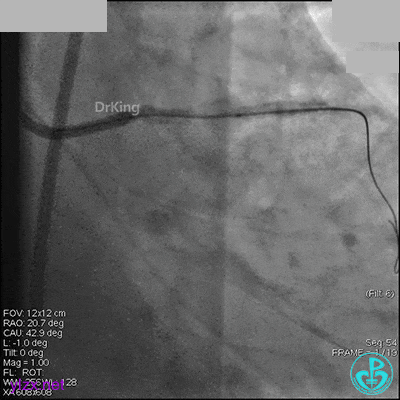

右冠脉中段充分扩张后欲植入3.5×38mm支架时,支架难以通过中远段扭曲处,且指引导管、导丝弹出飞扬。反复尝试导丝重新到达右冠脉远端时通过不顺利,局部造影剂滞留,远端血流接近3级。

右冠脉血流3级,患者无症状,终止手术。